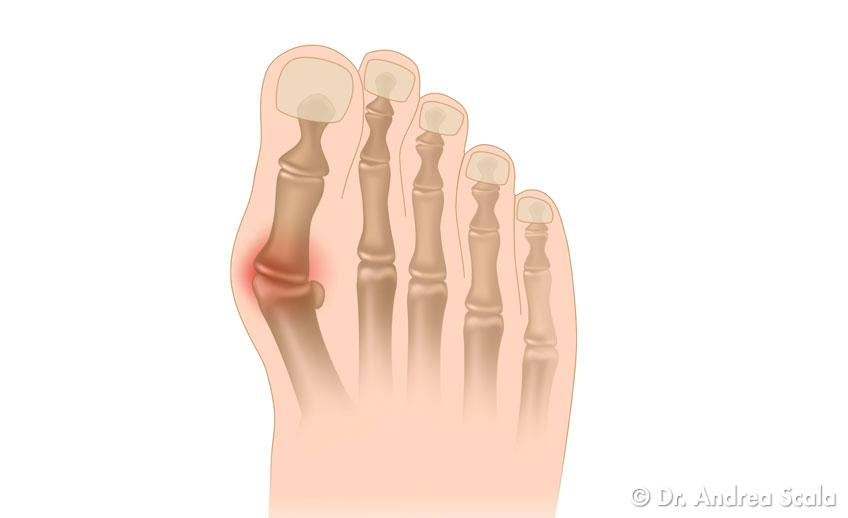

L’alluce rigido è l’artrosi della articolazione dell’alluce. L’alluce colpito dalla malattia si blocca e diviene molto doloroso ed infiammato. Colpisce maggiormente il sesso femminile.

L’alluce rigido è infatti una patologia infiammatoria-degenerativa a carico dell’articolazione metatarso-falangea. Questa patologia porta ad una riduzione della mobilità dell’alluce, con un dolore importante, a volta talmente forte da impedire una corretta deambulazione.

L’aspetto tipico dell’alluce rigido è la tumefazione dorsale sull’alluce a livello dell’articolazione. L’altra caratteristica è il blocco della articolazione che rimane fissa e non si muove dorsalmente. La deambulazione è difficile cosi come indossare le scarpe. L’attività sportiva alle volte rimane impossibile da effettuare.